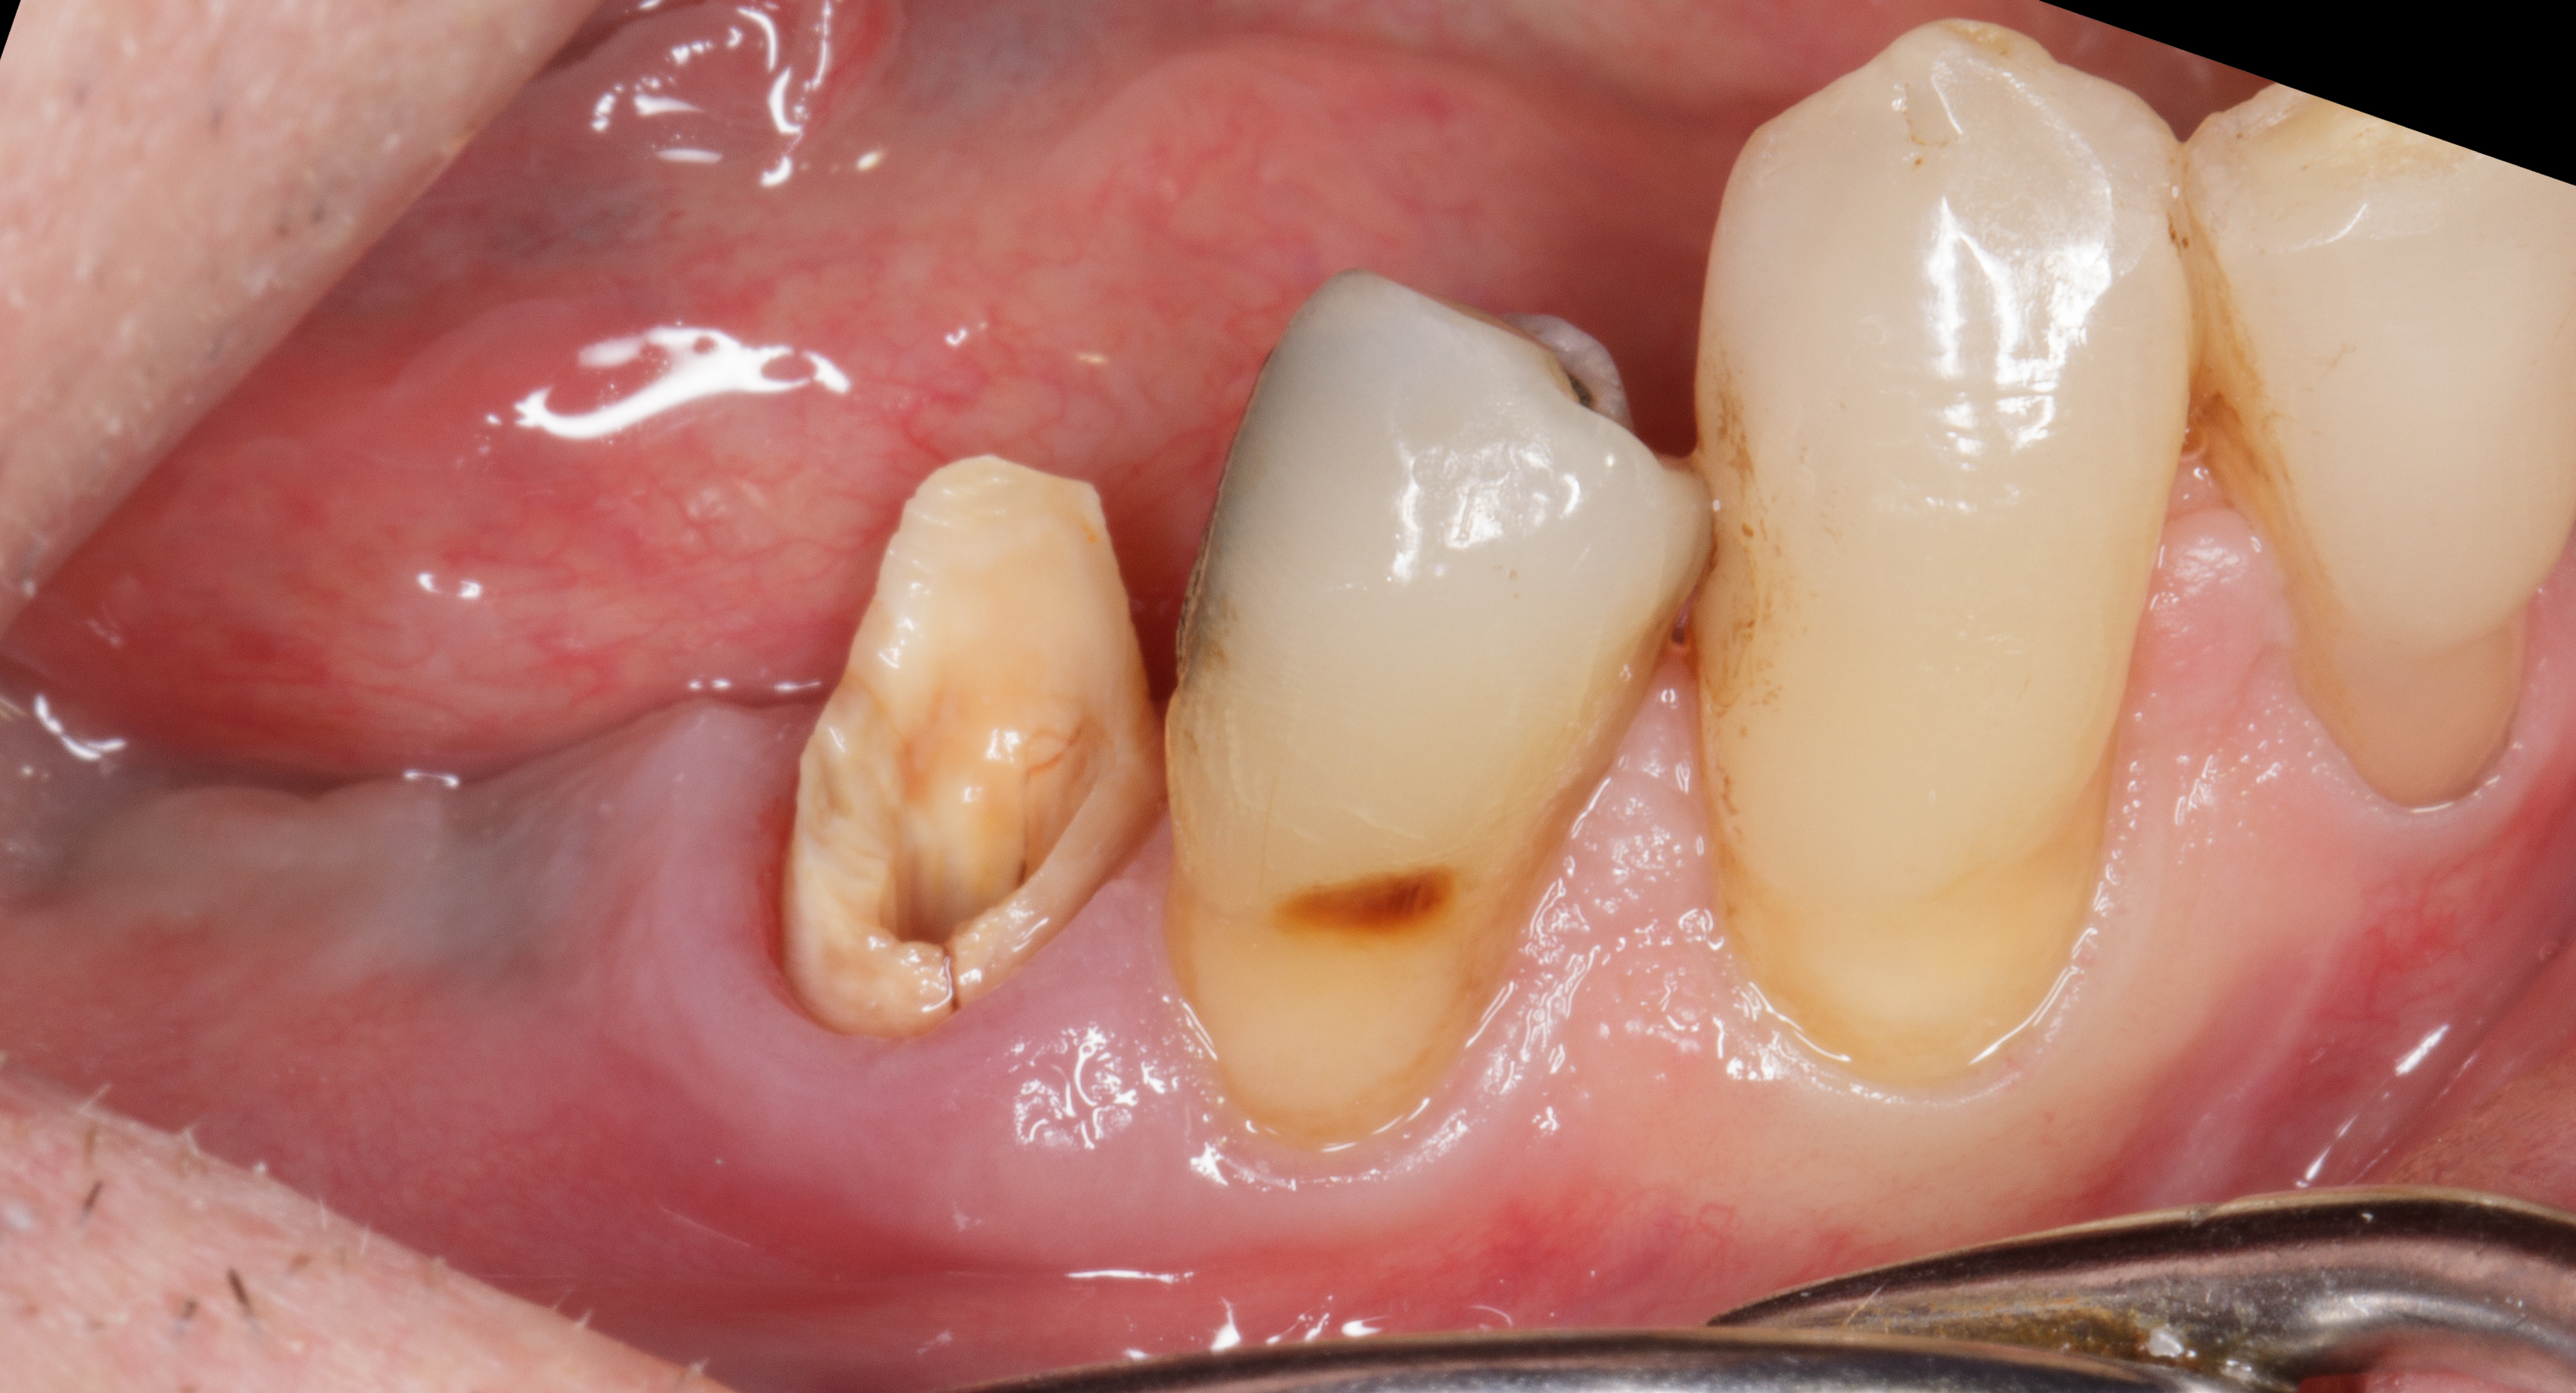

Il paziente si presenta alla nostra osservazione con l’elemento dentale 4.5 fratturato in senso verticale.

La situazione clinica appare essere la seguente: 4.5 elemento di ponte protesico con 4.6 in estensione, presenza di fistola vestibolare, sondaggio di 7 mm mesiale a radice di 4.5 fratturata con fuoriuscita ematica e purulenta (Figure 3-4).

Dopo terapia causale del quadrante inferiore destro e miglioramento della situazione parodontale, si procede alla rimozione delle corone protesiche 4.5 e 4.6.

Si evidenzia chiaramente la frattura radicolare corono-apicale dell'elemento 4.5 (Figure 5-6).